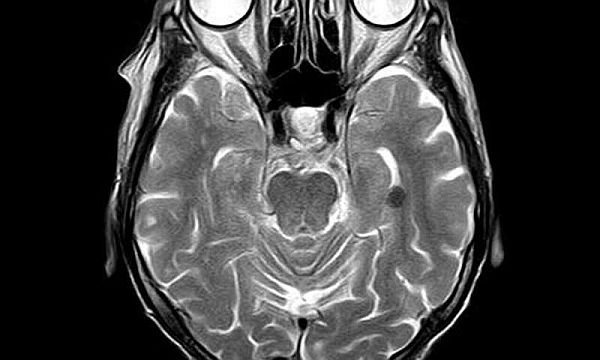

Chế tạo máy chụp cộng hưởng từ não có thể di động với giá thành rẻ

Khi nói đến chụp cộng hưởng từ não để đánh giá chấn thương ở đầu, phát hiện ung thư não và thực hiện nhiều xét nghiệm khác, thì chụp cộng hưởng từ (MRI) là lựa chọn tốt nhất, nhưng máy MRI có giá thành đắt đỏ, cần đến hạ tầng đặc biệt và không di động. Giờ đây, một nhóm nghiên cứu tại Bệnh viện Đa khoa Massachusetts đã chế tạo được máy MRI "chỉ dành cho đầu" có giá thành rẻ, công suất thấp, nhỏ gọn, di động để gắn trong xe cứu thương, có thể đẩy vào phòng bệnh, đưa vào phòng khám tư hoặc bệnh viện bằng bánh xe. Nghiên cứu đã được công bố trên tạp chí Nature Biomedical Engineering.